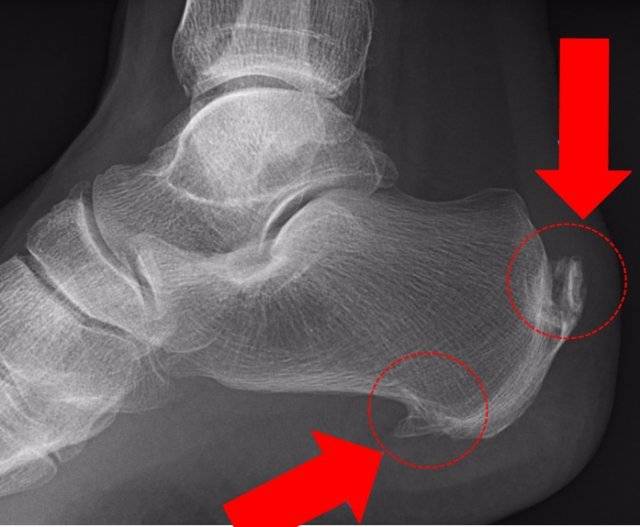

송 원장은 “운동에 중요한 역할을 하는 관절 건강도 살핀 뒤 운동해야 100세까지 즐길 수 있다”고 말했다. 무릎 및 발목 MRI(자기공명촬영)를 찍어보고 연골, 인대, 건 등에 문제가 있는지 살펴보고 몸 상태(체중, 키, 자세 등)에 따라 맞은 운동을 해야 부상을 막고 운동을 즐길 수 있다는 얘기다.